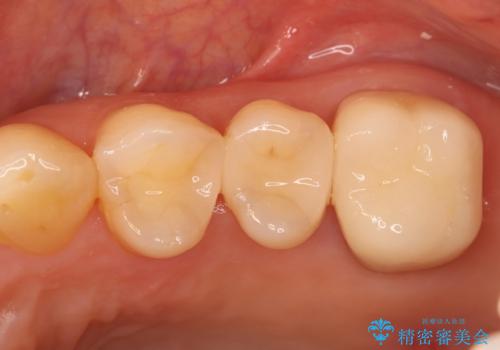

銀歯からセラミックへ。右上奥歯の精密根管治療と審美修復

担当医 河口智英